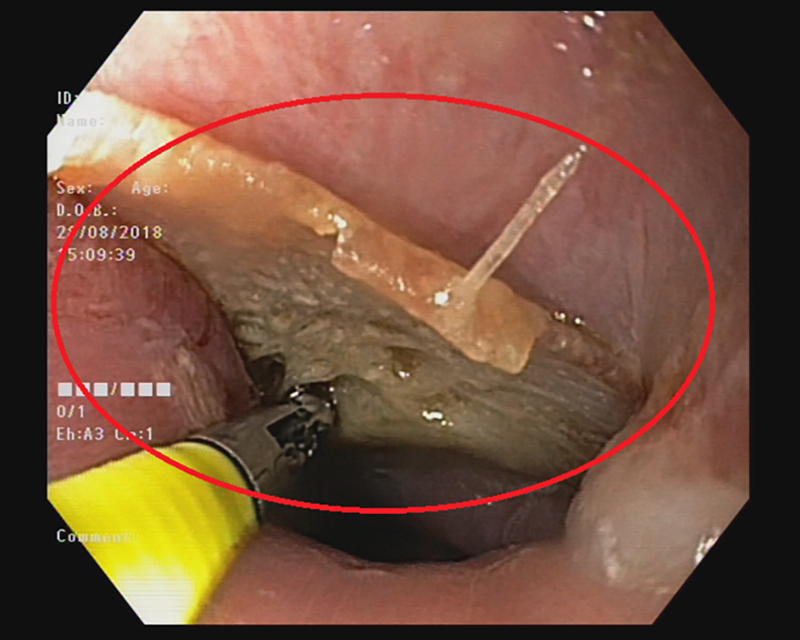

Đây có thể được coi là ca tai nạn sinh hoạt hy hữu mà BV trên tiếp nhận. Bệnh nhân vào BVXA-VL cấp cứu trong tình trạng khó chịu và đau cổ dữ dội. Sau khi thăm khám kỹ lưỡng, kiểm tra trên lâm sàng và nội soi, các bác sĩ phát hiện có hình ảnh của một mảnh xương cá nằm tại vị trí miệng thực quản.

Ngay sau đó các bác sĩ trung tâm nội soi tiến hành nội soi gắp xương cá. Hiện tại, tình trạng sức khỏe bệnh nhân đã ổn định và đã xuất viện trong ngày.

Các bác sĩ cho biết, mặc dù, xương cá là một dị vật thường gặp và đơn giản, nhưng nếu không được xử trí lấy dị vật ra kịp thời thì có thể sẽ xảy ra các tình huống nguy hiểm như dị vật đâm rách, thủng thực quản dẫn đến áp xe thực quản. Ổ áp xe có thể vỡ vào trung thất gây nguy hiểm đến tính mạng nhiều trường hợp có thể dẫn đến tử vong. Dị vật có thể di chuyển theo đường tiêu hóa xuống ruột gây tổn thương như rách thủng niêm mạc ruột, tắc ruột ảnh hưởng lớn tới sức khỏe. Khi đó việc can thiệp lấy ra bằng phương pháp nội soi vô cùng khó khăn thậm chí bệnh nhân phải trải qua một cuộc phẫu thuật phức tạp hơn.